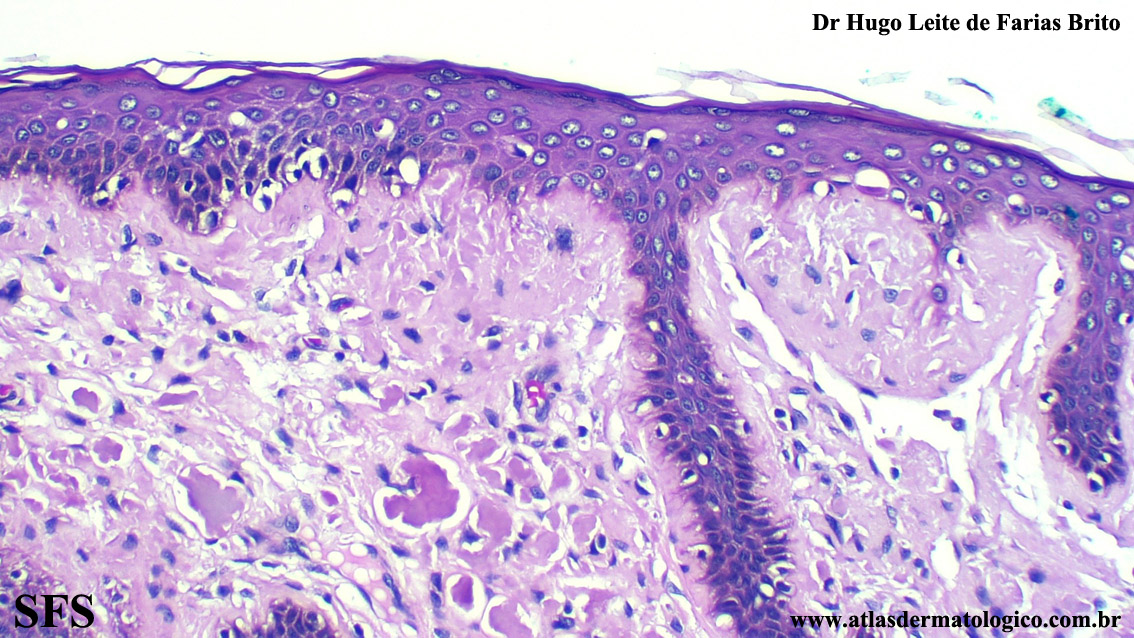

amyloidosis-nodular amyloidosis